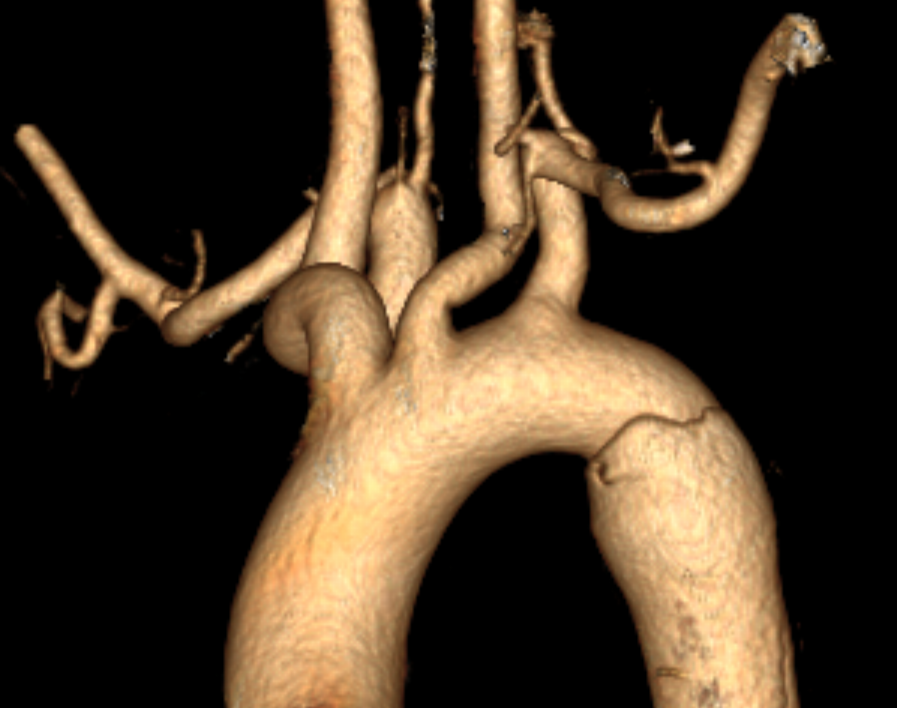

术前三维重建

术前术后三维重建对比